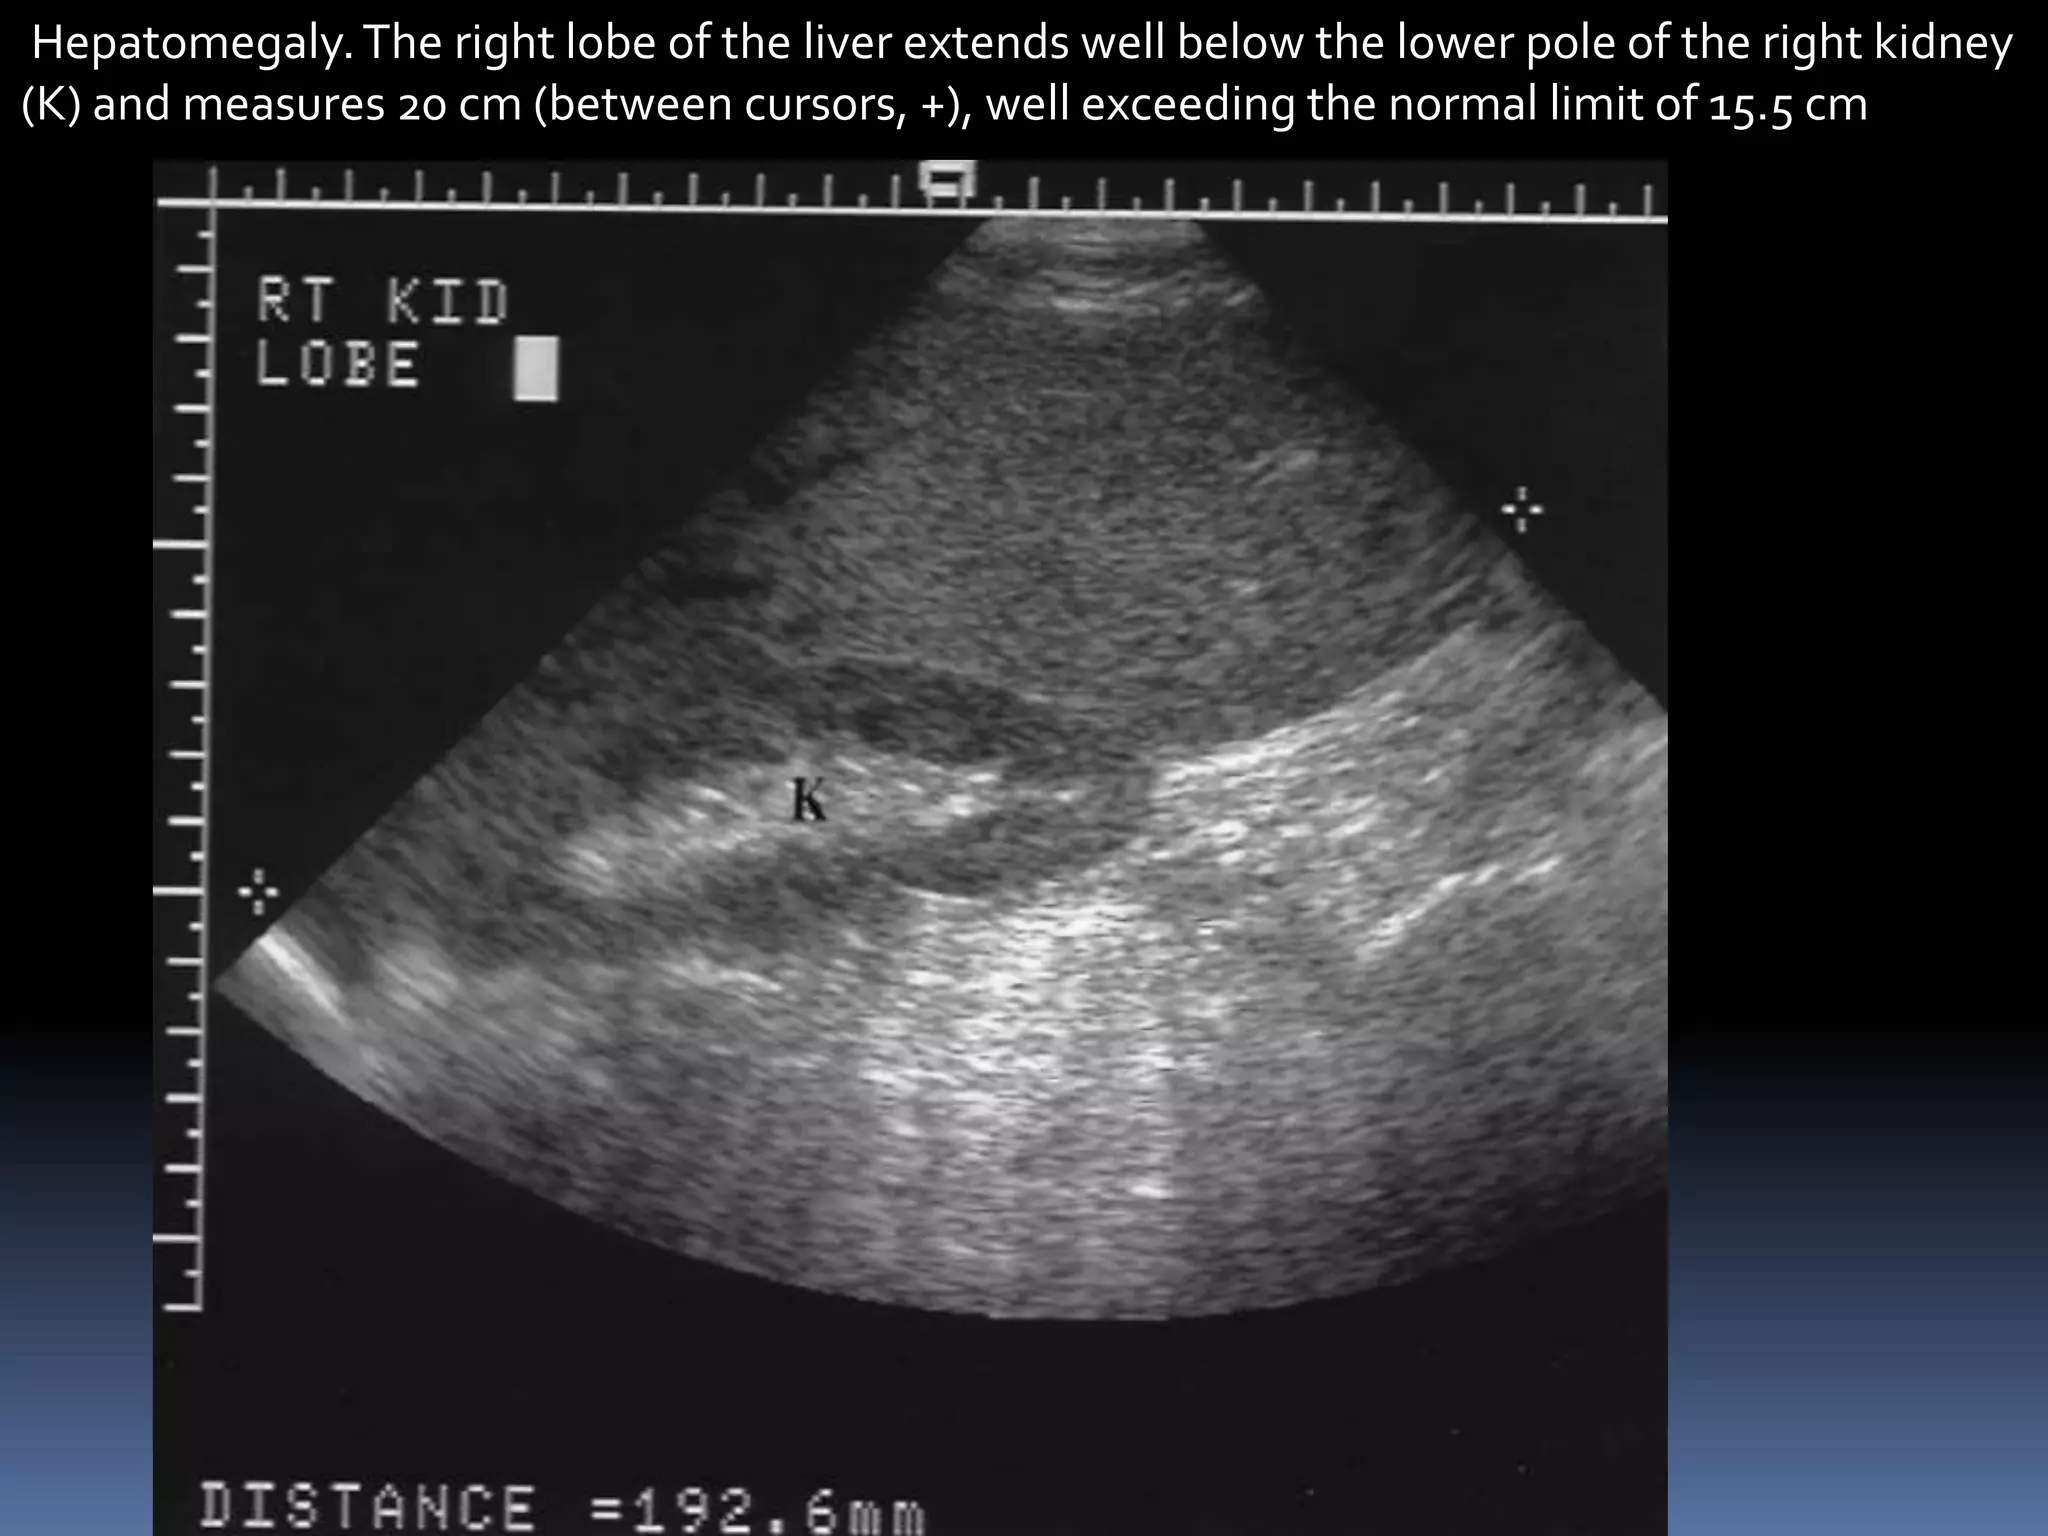

Hepatomegaly.The right lobe of the liver extends well below the lower pole of the right kidney

(K) and measures 20 cm (between cursors, +), well exceeding the normal limit of 15.5 cm